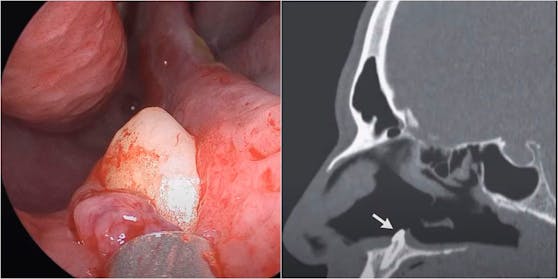

Bei der Untersuchung wurde festgestellt, dass der Patient eine Nasenscheidewandverkrümmung hatte, bei der die Trennwand zwischen den Nasengängen zur Seite geschoben ist. Ebenso wurden knochenartige Wucherungen in der Nase gefunden. Und das, obwohl der Patient keine sichtbaren Traumata oder Anomalien im Gesicht aufwies. Um dem Problem auf den Grund zu gehen, führten die Mund-, Kiefer- und Gesichtschirurgen Sagar Khanna und Michael Turner eine Rhinoskopie durch – eine Nasenuntersuchung, die mit einem röhrenförmigen Instrument mit Licht und Linse durchgeführt wird. Sie entdeckten eine "harte, nicht empfindliche, weiße Masse", die durch "den Boden des rechten Nasenlochs" ragte. Laienhaft ausgedrückt: Ein Schneidezahn in der Größe von 15 Millimeter.

Die Ursache für diesen Eindringling ist nach wie vor unklar. Glücklicherweise waren die Ärzte in der Lage, den Zahn des Patienten durch eine invasive intra-nasale Operation zu entfernen, ohne dass es zu "postoperativen Komplikationen" kam, heißt es in dem Bericht. Und bei einer "Nachuntersuchung drei Monate nach der Operation waren die Symptome der nasalen Blockade beim Patienten verschwunden."